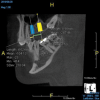

(8.) An original finding of a small lesion on the mesial root of tooth No. 30 was not accompanied by any outward symptoms; therefore, the patient delayed pursuing treatment. When a follow-up CBCT scan was acquired 6 years later, the easy-to-visualize increase in the dimensions of the lesion motivated the patient to elect a treatment plan.

Figure 8

(9.) An original finding of a small lesion on the mesial root of tooth No. 30 was not accompanied by any outward symptoms; therefore, the patient delayed pursuing treatment. When a follow-up CBCT scan was acquired 6 years later, the easy-to-visualize increase in the dimensions of the lesion motivated the patient to elect a treatment plan.

Figure 9